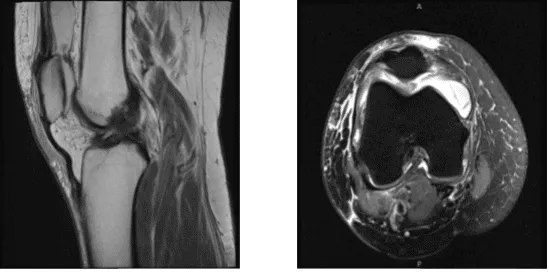

MRI reviewed and discussed by the doctor; Intra-articular body seen within the suprapatellar bursa measuring 10.2 mm. soft tissue edema seen within the superficial soft tissues surrounding the right knee.

Large effusion has no popliteal cyst is visualized and no evidence of stress injury, fracture, osteonecrosis or osseous neoplasm. No arthritic changes are visualized, the medial meniscus is unremarkable in MR appearance, without evidence of degeneration or tear.

The lateral meniscus is unremarkable in MR appearance, without evidence of degeneration or tear. The ACL, PCL, collateral ligaments, iliotibial band, fibular collateral ligament and biceps femoris tendon, popliteus muscle-tendon unit are all unremarkable.

The patella is inferiorly displaced with wavy patellar tendon and associated tear of the medial quadriceps. The impression of this is the Medial quadriceps tear, Cruciate ligaments and menisci are intact, the Intra-articular body in the superior patella bursa measuring 10.2 mm. and has Effusion.

MRI was done, it showed osteoarthritic changes and which showed a loose body in the suprapatellar pouch. We discussed treatment options and the patient opted for surgical management.

MRI-3T Right knee non-contrast